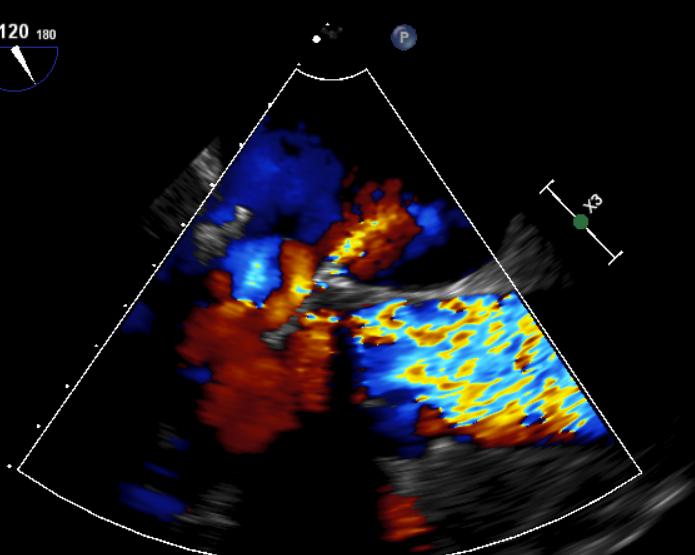

原生物瓣少量反流

过瓣流增快,呈“五彩状”

CDFI提示过瓣血流通畅

CDFI示少量瓣周漏

收缩期未见瓣周漏